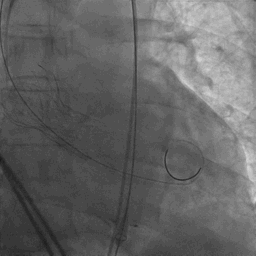

TaurusOne®轻松过弓

TaurusOne®释放过程:

瓣膜定位